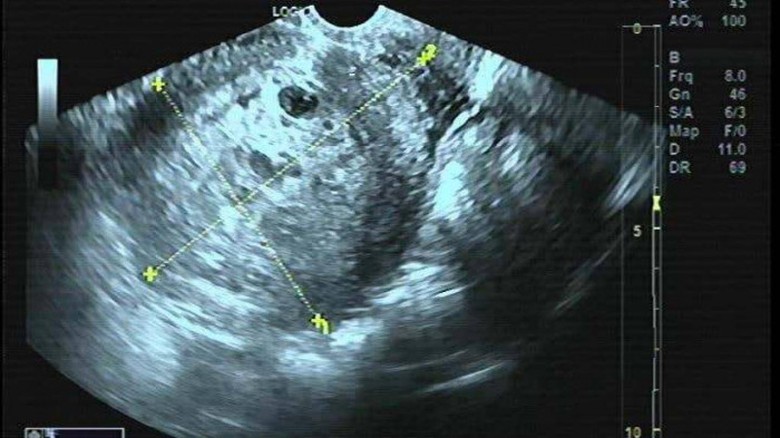

Kết quả siêu âm, xét nghiệm cho thấy bệnh nhân chửa trứng, chỉ định phẫu thuật cắt tử cung

Tại đây, bệnh nhân được thăm khám và làm các xét nghiệm, và được chẩn đoán chửa trứng và đã phẫu thuật cắt tử cung ngay sau đó. Hiện tại, sức khỏe của bệnh nhân ổn định, cần phải theo dõi chỉ số Beta - hCG định kỳ theo hướng dẫn để phòng biến chứng.

ThS.BS Nguyễn Thị Hiền - Chuyên khoa Sản, BV ĐK Medlatec giải thích về hiện tượng thai trứng: Đây là tình trạng thai nghén bất thường, trong đó một phần hay toàn bộ gai rau bị thoái hóa thành các túi chứa dịch to, nhỏ, dính vào nhau thành từng chùm giống như chùm nho. Đa số trường hợp không có bào thai (thai trứng hoàn toàn), một số trường hợp có bào thai (thai trứng bán phần).